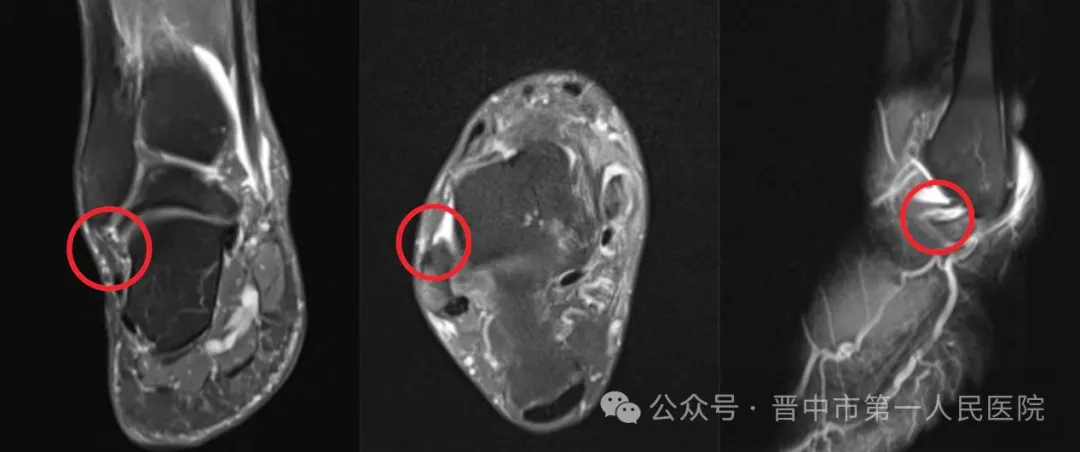

患者长期反复崴脚,伴随踝关节疼痛和活动受限,严重影响日常生活,就诊于晋中市第一人民医院骨科胡德亚主任医师门诊。经影像学检查,确诊为踝关节慢性不稳、距腓前韧带损伤、距骨骨髓水肿。

胡德亚介绍,患者的核心问题是韧带损伤后踝关节稳定性丧失,反复扭伤导致距骨持续受力异常,引发骨挫伤和撞击症状,若不及时干预,可能发展为骨关节炎等不可逆损伤。面对复杂病情,骨科团队联合磁共振室、CT室进行多学科会诊与术前评估,最终制定关节镜下微创手术方案。